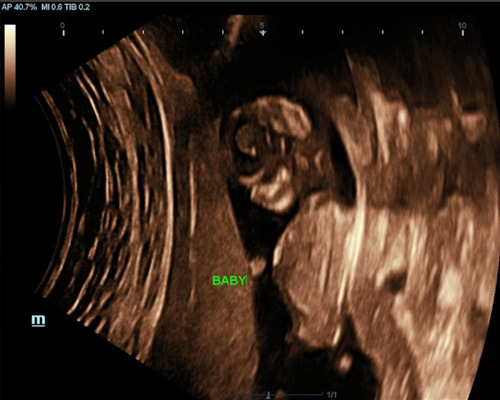

Usually performed between 6 and 12 weeks, a pregnancy viability scan uses ultrasound to check key aspects of early pregnancy. During the scan, the sonographer confirms the pregnancy location in the uterus, checks for your baby’s heartbeat when visible, measures the embryo to estimate gestational age, and identifies whether it is a single or multiple pregnancy.

This early pregnancy scan helps provide clarity and reassurance, and for many parents, seeing their baby’s heartbeat during a viability scan near Nottingham becomes a special milestone in their pregnancy journey.